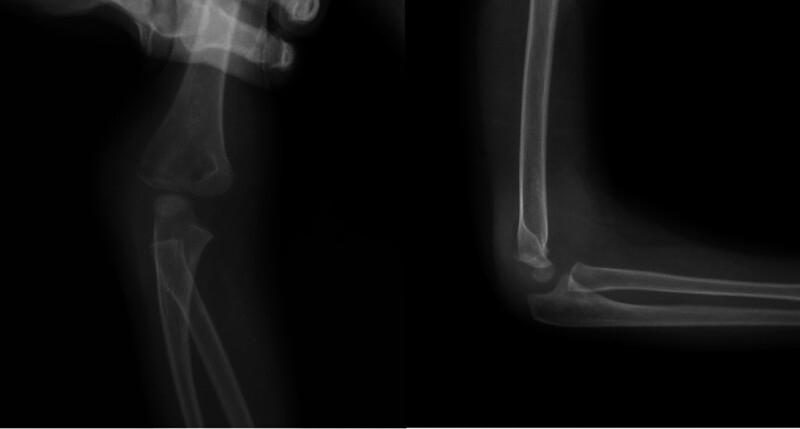

小儿肱骨外侧髁骨折(PHLCF)是儿童中最常见的骨折之一。PHLCF约占所有小儿肘部骨折的20%。治疗方法包括:夹板固定的非手术治疗、经皮K线固定闭合复位术(CRPP)和K线固定开放复位术(ORIF)。我们的目的是评估采用 CRPP 或 ORIF 治疗 Jakob 2 型 PHLCF 的放射学、功能和临床疗效。我们假设 CRPP 与 ORIF 对 Jakob 2 型 PHLCF 的治疗同样安全有效。在这项回顾性研究中,我们纳入了在一个中心接受手术治疗的 Jakob 2 型 PHLCF 患者。研究排除了多发性骨折或开放性骨折患者。研究共纳入 69 名 2 至 12 岁的患者,并将他们分为两组。第一组包括接受 CRPP 治疗的患者,第二组包括接受 ORIF 治疗的患者。研究人员对患者的人口统计学、放射学、临床和功能参数进行了评估。平均手术时间(P

Pediatric humerus lateral condyle fractures (PHLCF) are one of the most common fractures among children. PHLCF is approximately 20% of all pediatric elbow fractures. Among the treatment modalities are: nonoperative treatment with splinting, closed reduction with percutaneous K-wire fixation (CRPP), and open reduction with K-wire fixation (ORIF). We aimed to evaluate radiological, functional, and clinical outcomes of Jakob type 2 PHLCF treated either with CRPP or ORIF. We hypothesized that CRPP may be as safe and effective as ORIF for Jakob type 2 PHLCF. In this retrospective study, we included patients with Jakob type 2 PHLCF operatively treated in a single center. Patients with multiple fractures or open fractures were excluded from the study. 69 patients between ages 2 and 12 were included and they were divided into two groups. Group 1 included the patients treated with CRPP, whereas Group 2 included the patients treated with ORIF. Demographical, radiological, clinical, and functional parameters were evaluated. Average duration of surgery ( P  < 0.001), initial displacement ( P  = 0.014), and duration of admission ( P  < 0.001) were significantly less in group 1. Group 2 had significantly higher percentage of left-sided injury than group 1 ( P  = 0.038). Average varus deformity score was significantly higher in group 1 ( P  = 0.014). CRPP was associated with shorter duration of surgery and hospital stay. Functional, clinical, and radiological outcomes were identified similar between CRPP and ORIF for Jakob type 2 PHLCF. CRPP may be as safe and effective as ORIF for Jakob type 2 PHLCF.